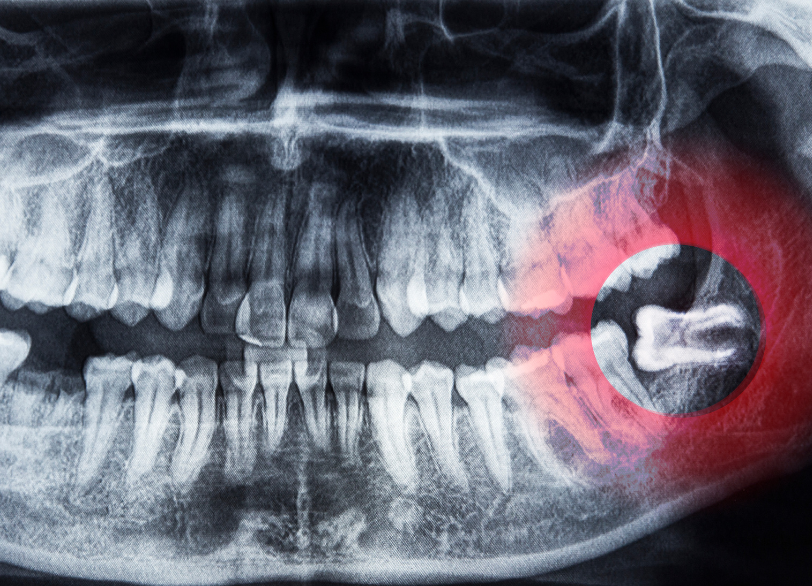

こだわり①すべては、精密な診査・診断から始まります

歯科用CTによる、三次元での徹底分析

特に下の親知らずの抜歯において最も注意しなくてはならないのがすぐ近くを走行している「下歯槽神経(かしそうしんけい)」という太い神経との位置関係です。

従来の二次元的なレントゲン写真だけではこの神経と歯の根との正確な距離や位置関係を把握することは困難でした。

当院では必ず歯科用CTによる撮影を行います。

CTを用いることで歯の根の複雑な形や神経管との立体的な位置関係を0.1ミリ単位であらゆる角度から正確に把握することができます。

これにより術中に神経を傷つけてしまうといった偶発症のリスクを限りなくゼロに近づけることが可能になります。

この術前の「見える化」こそが安全な抜歯の絶対的な土台となるのです。